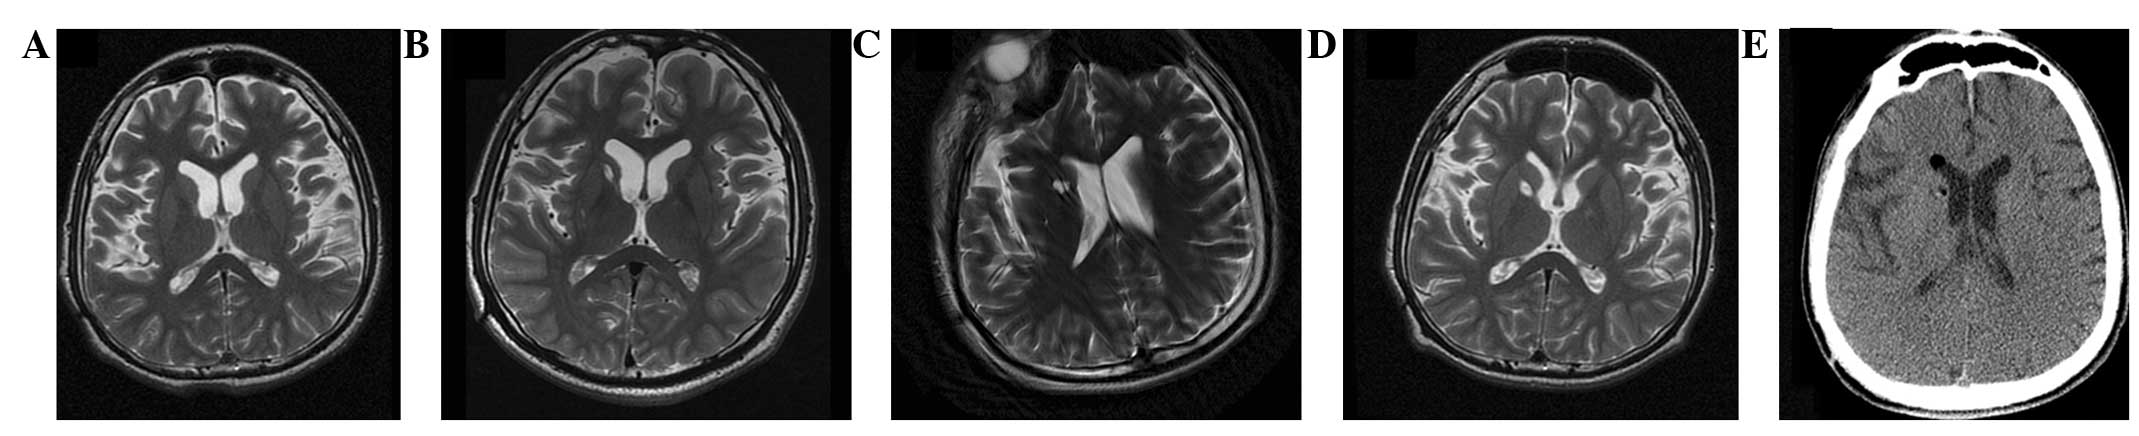

圖2:-T2加權磁共振成像 (MRI)

(A) 術前 MRI 顯示腦萎縮。 (BD)術后1年、3年、4年MRI與術前MRI相比無明顯變化。 (E) 術后3天,計算機斷層掃描顯示沒有出血或水腫。

CT(圖1b-e)和MRI(圖2b-d)掃描顯示4年隨訪期間沒有顯著變化。 手術前1天(圖1f)和手術后1、2、3和4年(圖1g-j) 獲得18F-FDGPET掃描。術后雙側植入部位豆狀核和丘腦18F-FDG攝取值較術前增加。這一結果表明,自移植以來,葡萄糖代謝逐年略有增加。